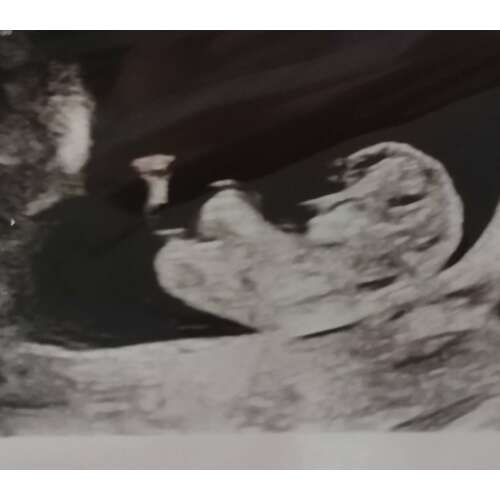

Hoi, dit was met de termijn echo (12 weken precies), ziet iemand hier de nub? Het echo apparaat is niet heel denderend helaas. We zijn gewoon nieuwsgierig 😊

Deze had ik in het vorige topic geplaatst. Het was nog even spannend wat het nu zou worden door mijn verwarring over het nubje! Voor de mensen die gereageerd hadden, het is een meisje!💗☺️

Oh deze is misschien beter.